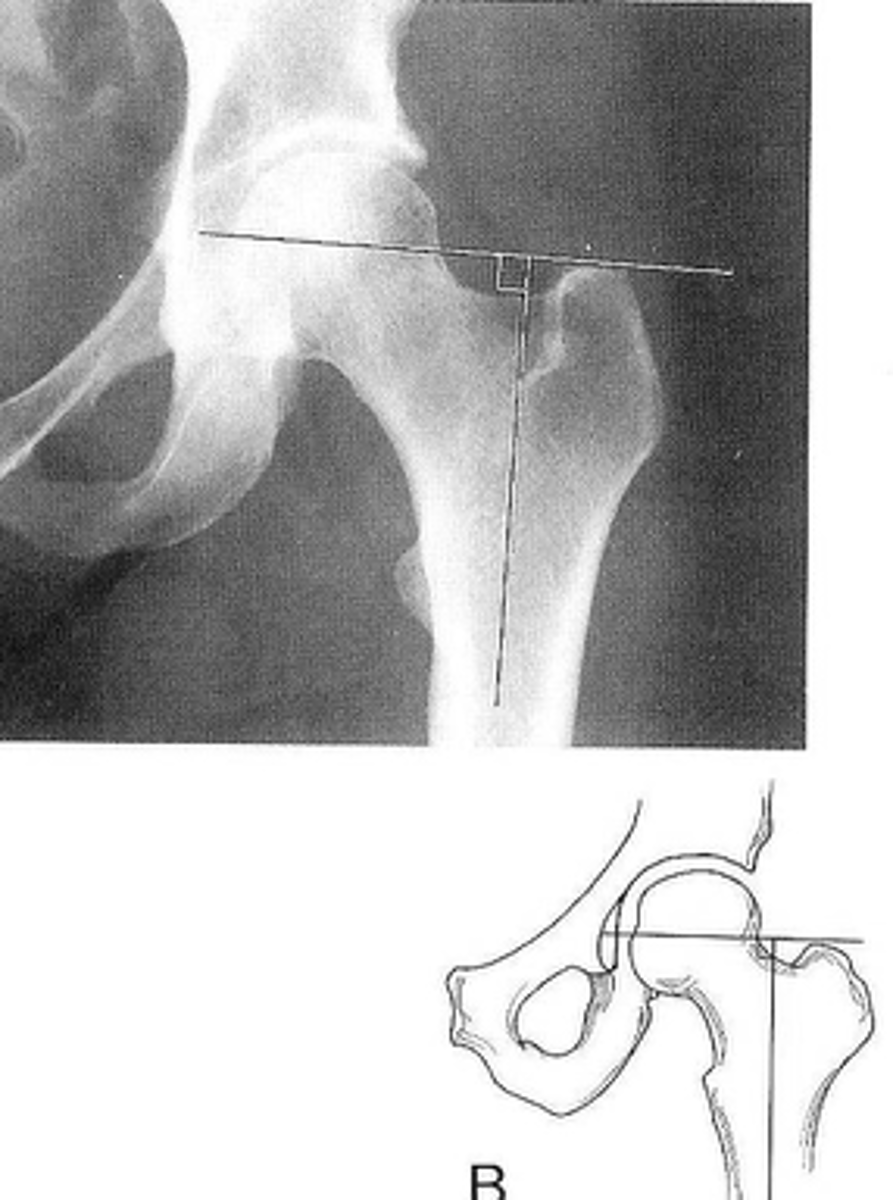

Kohler's teardrop distance

ID measurement line

<p>ID measurement line</p>

- AP pelvis

- AP hip

What views are needed to see Kohler's teardrop distance?

- Medial margin of femoral head

- Lateral border of teardrop

Kohler's teardrop distance landmarks

6-11 mm

Normal Kohler's teardrop distance measurement

<p>Normal Kohler's teardrop distance measurement</p>

2 mm

The normal Kohler's teardrop distance is 6-11 mm, and there should be no greater than a _____ difference when comparing to the contralateral side

<p>The normal Kohler's teardrop distance is 6-11 mm, and there should be no greater than a _____ difference when comparing to the contralateral side</p>

Hip joint effusion

Clinical significance of an enlarged Kohler's teardrop distance

<p>Clinical significance of an enlarged Kohler's teardrop distance</p>

Waldenstrom's sign

What sign indicates an enlarged Kohler's teardrop distance?

- Accentutation of the normal limits

<p>What sign indicates an enlarged Kohler's teardrop distance?</p><p>- Accentutation of the normal limits</p>

Intracapsular swelling/joint effusion

Waldenstrom's sign is usually an indication of _____

<p>Waldenstrom's sign is usually an indication of _____</p>

Inflammatory arthritis

Clinical significance of a small Kohler's teardrop distance

<p>Clinical significance of a small Kohler's teardrop distance</p>

Hip joint space width

ID measurement

<p>ID measurement</p>

Superior, axial, medial joint spaces (SAM)

Hip joint space width landmarks

<p>Hip joint space width landmarks</p>

3-6 mm

Normal superior hip joint space width

<p>Normal superior hip joint space width</p>

3-7 mm

Normal axial hip joint space width

<p>Normal axial hip joint space width</p>

4-13 mm

Normal medial hip joint space width

<p>Normal medial hip joint space width</p>

Joint effusion

Clinical significance of a wide hip joint space

<p>Clinical significance of a wide hip joint space</p>

Arthritis

Clinical significance of a narrow hip joint space

<p>Clinical significance of a narrow hip joint space</p>